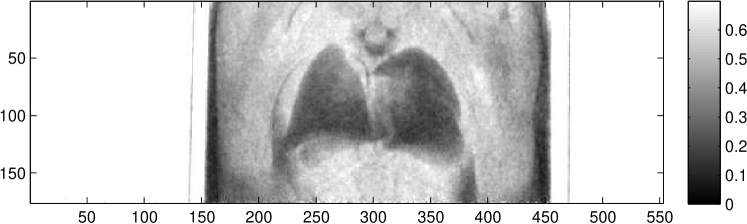

In situ lung imaging of two healthy C57BL/6 adult mice was performed to obtain information on the signals of phase-contrast imaging. Figure 3 shows the three images obtained of the lungs of a mouse in posterior-anterior (p.a.) orientation, using eight phase steps with and an acquisition time of each at a tube current of . This corresponds to an air kerma of measured at the object position with a calibrated IBA Dosimax plus A HV dosimeter with the solid-state detector unit RQX 70kV.

While the lung tissue is only weakly visible in the absorption image in Figure 3 the bony structure of the mouse thorax can clearly be seen. In the differential-phase image the fur of the animal is clearly visible. Both lungs as well as the spinal cord of the animal are shown. The speckle noise in the phase image described by Kitchen et al. (2004) can be observed in the expected lung area. Dark field imaging highlights clearly the fur-air interface as well as both lungs with their typical anatomical structures and sizes. Furthermore, the boundaries of the chest wall are clearly visible in the dark field and the differential-phase image.

These findings are supported by the images taken from the second mouse shown in Figure 4. While in the absorption image mainly the bones and the air-filled chest cavity can be seen, the other two images allow exact distinction between the empty chest cavity and the lung tissue.

First of all, three images containing different tissue properties are gained with one imaging process. This leads to an increase in information from which radiologists can make a more profound diagnosis. An example for the complementarity of information in the three images is shown in Figure 3. There, the absorption image is dominated by the bones of the animal and is therefore a good source for information about the skeletal structure and its diseases, like bone fractures. In the differential-phase image on the other hand, the bones are suppressed. Furthermore, the soft tissue contrast and the tissue edges are enhanced. This leads to a high organ visibility as in the differential-phase image of Figure 3 the lungs and the upper airways can be seen. The third image quantity, the dark field is a measure of the granularity of structures. Because of this, the lung, which consists of many alveoli, produces a high dark field signal.

Comparing the three images, it becomes obvious that the differential phase and the dark field image complement the absorption image and improve the identification of the shape of the lung. Especially in cases where the granularity of the lung tissue is affected, the dark field image can lead to a faster diagnosis and therefore treatment, as more information about the lung is accessible without a CT scan. It is imaginable for the identification of pulmonary oedema, where the alveoli are filled with water. This leads to a more homogeneous view of the lung and can, in combination with the higher absorption of the water visible in the absorption image, facilitate the diagnosis. Other examples for illnesses of the lung where the three different image quantities can possibly be exploited are lung cancer, pneumonia or pneumothoraxes. For the last one, example images are shown in Figure 4. In the latter, the area which is occupied by the lung is just a very small part of the chest cavity. This area can clearly be identified in the dark field projection image, while in the absorption image the contrast between space with and without lung tissue is hardly visible.